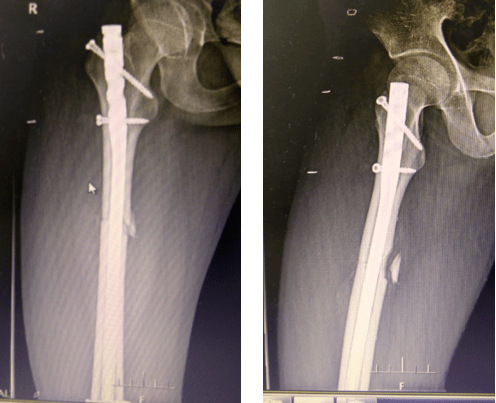

肱骨多段骨折髓内钉固定一例

最近做的一例肱骨髓内钉,请指教 [病例帖]